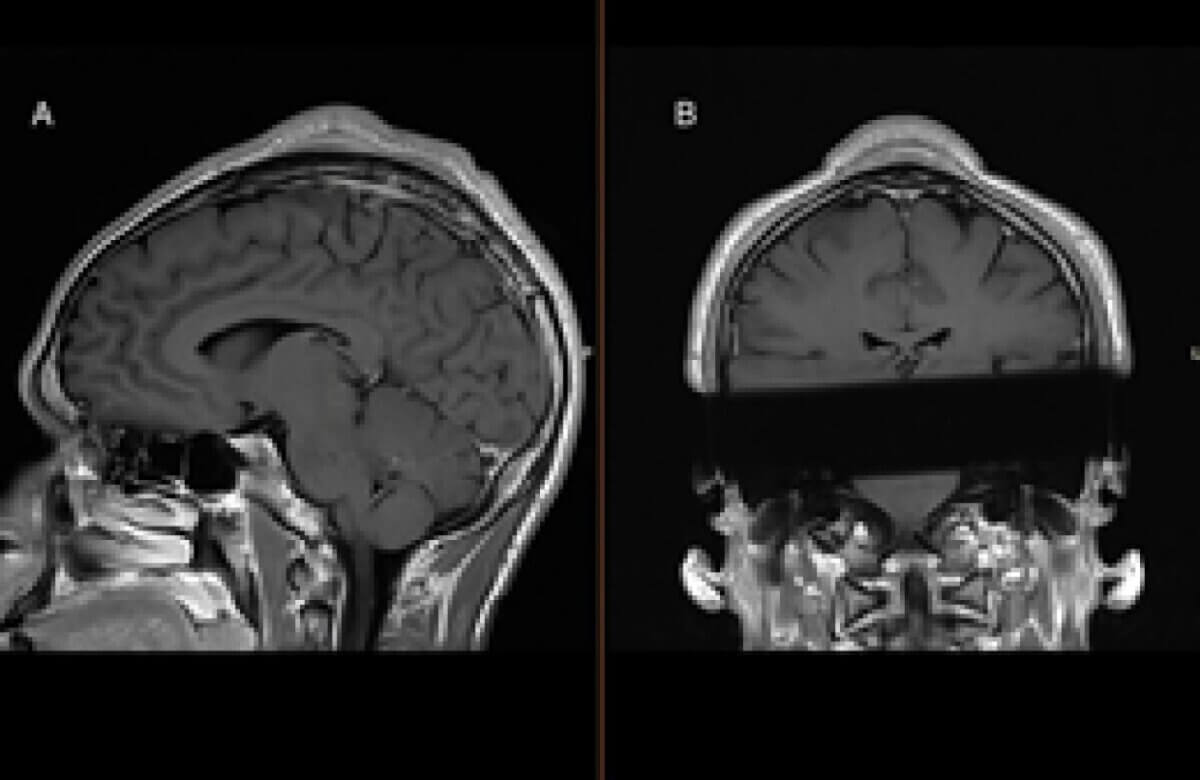

Upon examination, doctors discovered a longitudinal mass at the vertex of the patient’s skull. MRI scans revealed significant subgaleal fibrosis and thickening of the subcutis (the layer of tissue right under the skin), consistent with what radiologists call the “cone-head sign.” This sign is characterized by a cone-shaped deformity at the top of the skull, resulting from repeated trauma to the area.

The MRI revealed a subgaleal mass measuring 33.4 Ă— 0.6 Ă— 2.9 cm near the midline vertex of the skull. The skin and subcutaneous tissue were thickened above this mass, and the skull underneath showed slight thickening compared to surrounding areas. Histological analysis of the removed tissue showed extensive fibrosis but no signs of cancer. At a one-month follow-up appointment, the patient reported high satisfaction with the surgical outcome.